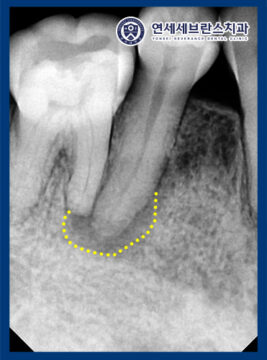

자세한 확인을 위해

엑스레이 사진을 촬영해 보니,

치아 뿌리 끝 염증을

관찰할 수 있었습니다.

또한 엑스레이 상 뒤쪽 치아까지

염증이 이환된 것으로 보이나,

신경이 살아있는 것으로 확인되어

앞 치아만 진행하고 추후 통증 발생 시

추가로 신경치료를 진행하기로 하였습니다.